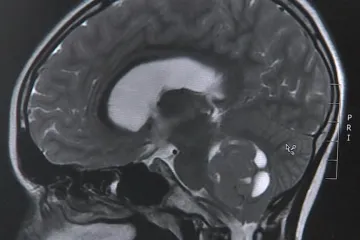

Na Homolce mají vylepšený gama nůž. Lékaři si s ním troufnou i na složité nádory